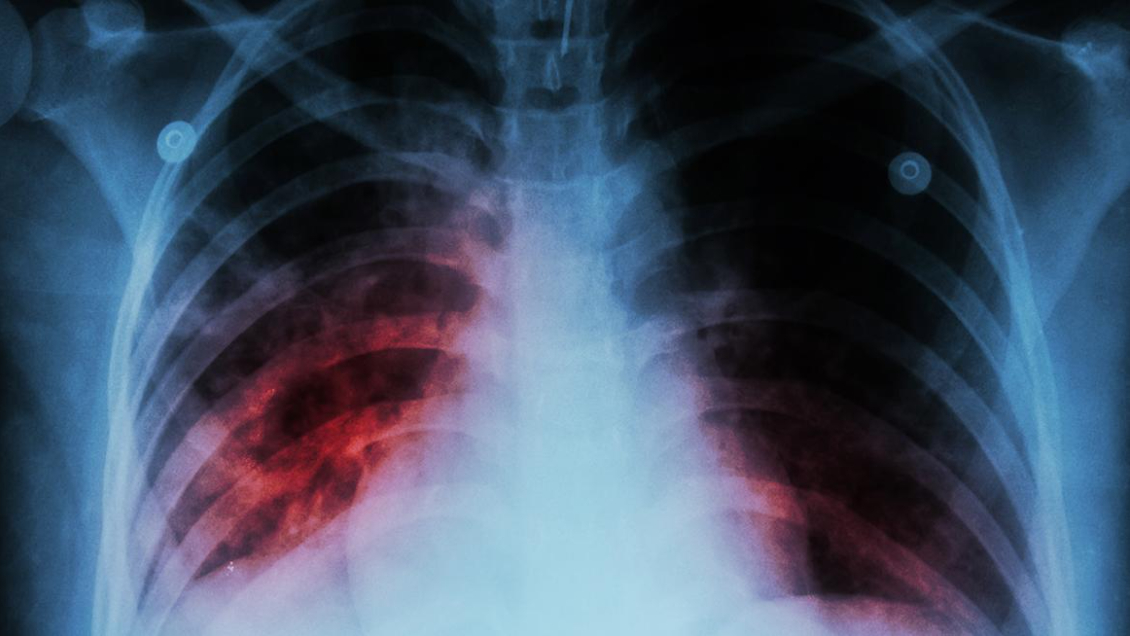

Casi 50 trabajadores de la salud se infectaron de tuberculosis en Venezuela

Referencial

Al menos 46 trabajadores sanitarios del sector público de Venezuela se infectaron de tuberculosis entre enero y junio de este año, según un reporte de la Encuesta Nacional de Hospitales (ENH) publicado este jueves y elaborado por la ONG Médicos por la Salud.

La organización señaló que los casos se tratan de "diagnósticos presuntivos clínicamente y no de casos confirmados", pues en Venezuela "no hay reporte semanal epidemiológico desde 2015".

El reporte no confirma que los sanitarios se infectaron en sus lugares de trabajo, pero sí reitera el deterioro de la red hospitalaria pública, en la que escasean medicamentos y elementos como mascarillas y guantes.